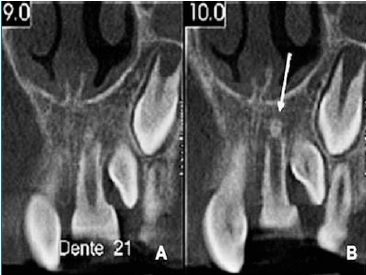

After 3 months of follow-up, the tooth presented a slight metallic sound to the percussion test, and the crown’s color was normal. No signs of ankylosis were observed in the periapical radiograph (Figure 4), and the tooth continued non-responsive to the cold test. In the fourth month of follow-up, the tooth exhibited slight mobility, but no other signs or symptoms were observed. Six months after the trauma, a positive response to the sensibility test was verified. After 9 months, the percussion test suggested ankylosis. The color of the tooth remained stable (Figure 5). A cone beam computed tomography (CBCT) suggested a formation of calcified tissue in the root’s apical third (Figure 6). At the 1-year follow-up, a periapical radiograph showed external root resorption in the cervical third of 21 (Figure 7). The patient did not exhibit fistula, gingivitis, pain, or any change in tooth color. The tooth was in infra-occlusion, and the clinical crown was 7 mm long.

Figure 6 CBCT images 9 months post-replantation. A - Left maxillary central incisor (21). B - Arrow shows calcified tissue in the periapical region of tooth 21.